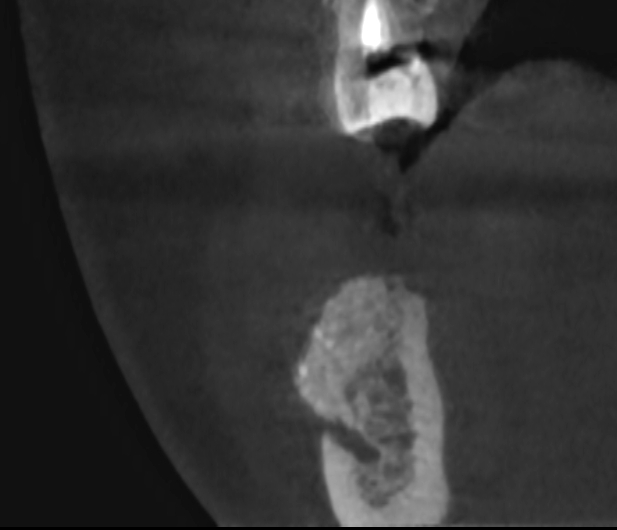

Ryc. 12. Skan tomografii stożkowej w okolicy 45, w 10 dobie po zabiegu.

Po okresie 6 miesięcy wykazano prawidłową resorpcję cementu i regenerację wyrostka poprzez odtworzenie kości żywiciela (pacjenta) do szerokości około 8 mm (ryc.13).

Ryc. 13. Regeneracja blaszki korowej przedsionkowej i deficytu kości w okolicy 45-46 6 miesięcy po zabiegu.